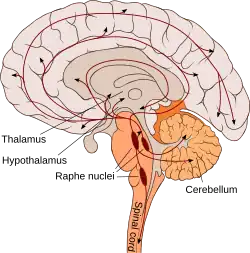

| Urin | 900–1300[23] |

Im menschlichen Organismus kommt die größte Menge an Serotonin im Magen-Darm-Trakt vor. Hier werden etwa 95 % der gesamten Serotoninmenge des Körpers, die auf 10 mg geschätzt wird, gespeichert. Etwa 90 % des Serotonins des Magen-Darm-Trakts werden in den enterochromaffinen Zellen gespeichert, die übrigen 10 % sind in den Nervenzellen (Neuronen) des Darmnervensystems zu finden.[25] Das Serotonin des Bluts ist fast ausschließlich auf die Thrombozyten (Blutplättchen) verteilt.[24] Dieses Serotonin wird von den enterochromaffinen Zellen des Magen-Darm-Trakts produziert und nach Abgabe in das Blut von den Thrombozyten aufgenommen. Auch basophile Granulozyten und Mastzellen können, zumindest bei Nagetieren, Serotonin speichern und freisetzen.[26][27] Im Zentralnervensystem befindet sich Serotonin insbesondere in den Neuronen der Raphe-Kerne. Eine pathologisch vermehrte Produktion, Speicherung und Freisetzung von Serotonin kann häufig bei neuroendokrinen Tumoren des Magen-Darm-Trakts, den Karzinoiden, beobachtet werden und ist für deren charakteristische Begleitsymptomatik verantwortlich.[28]

Zentralnervensystem

Serotonin, das sich im Zentralnervensystem in den Zellkörpern, den Somata serotoninerger Nervenbahnen in den Raphe-Kernen befindet, deren Axone in alle Teile des Gehirns ausstrahlen, beeinflusst unmittelbar oder mittelbar fast alle Gehirnfunktionen. Zu den wichtigsten Funktionen des Serotonins im Gehirn, das die Blut-Hirn-Schranke nicht überwinden kann und daher vor Ort gebildet werden muss, zählen

Schlaf-Wach-Rhythmus

Eine mögliche Rolle des Serotonins bei der Regulierung der Schlaf-Wach-Rhythmik ist seit den 1950er Jahren bekannt. Die Befunde zur Modulation der Schlaf-Wach-Rhythmik durch Serotonin waren lange Zeit teils widersprüchlich.[62] Nach heutigem Kenntnisstand bewirkt Serotonin im Wesentlichen die Beförderung des Wachzustands.[63] Dabei sind die serotoninhaltigen Neurone der Raphe-Kerne, welche mit dem Nucleus suprachiasmaticus (SCN) des Hypothalamus, dem Sitz der Hauptuhr der Säugetiere, verbunden sind, während des Wachzustands aktiv. Im Tiefschlaf hingegen reduzieren sie ihre Tätigkeit, und während des REM-Schlafs stellen sie diese praktisch ein.[64][65] Zugleich steuert der Nucleus suprachiasmaticus unter anderem die Produktion und Freisetzung des an der zeitlichen Steuerung des Schlafs beteiligten Hormons Melatonin aus der Zirbeldrüse.[66]